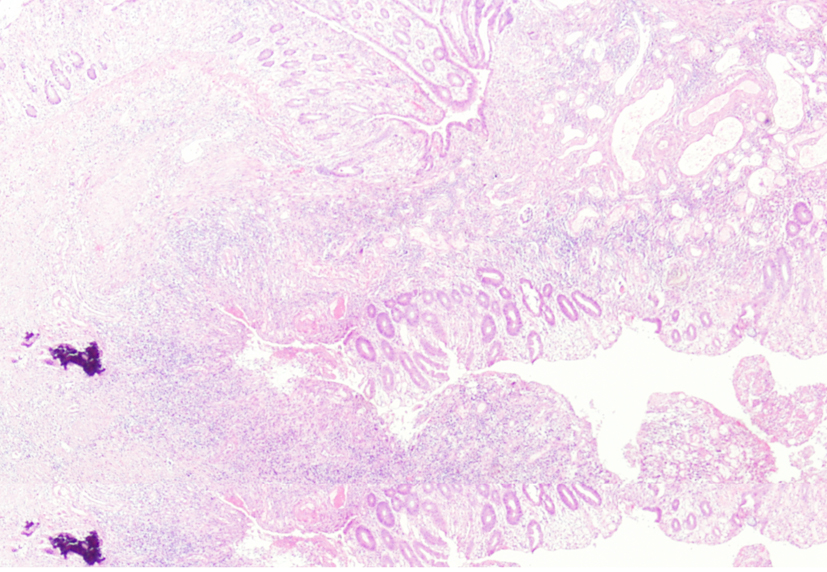

Intraoperative findings showed cystic and solid mass at the tail of pancreas with irregular shape measuring 10 × 8 × 7 cm. The mass had partially well-circumscribed margin and the rest was adhering to splenic hilum and adjacent segment of transverse colon. The cyst was dissected and was found to communicate with colon. Meantime, there was also opening of splenic artery rupture about 0.2 cm and distal splenic arterial pseudoaneurysm. So, splenectomy, pancreatic tail resection and splenic flexure resection were performed together. Histopathological examination showed pancreatic pseudocyst with chronic inflammation, multiple colonic ulcers and a perforation between pseudocyst and colon (Fig. 4). Post-operative course was uneventful and the patient was discharged from hospital on the postoperative 2 weeks. The patient was free of disease on the 2 years follow-up.

![]() Click for large image | Figure 4. Microscopic findings of resected specimen showed the formation of fistula associated with colonic inflammation reaction. |